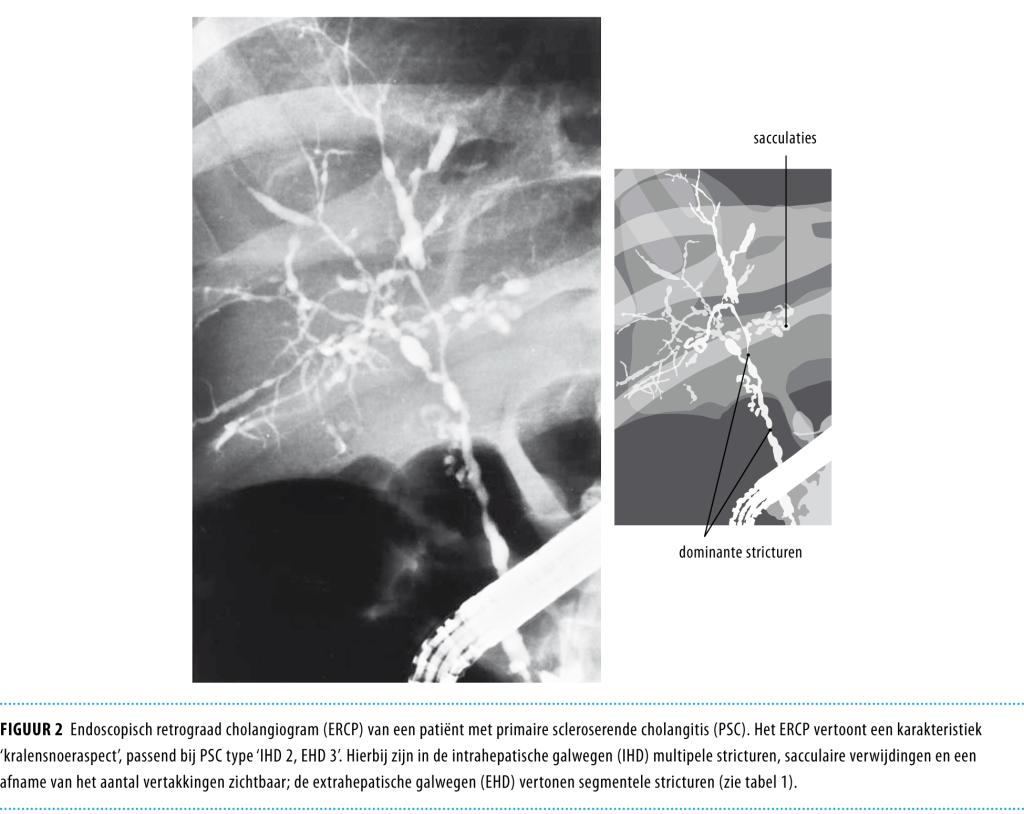

• De diagnose wordt gesteld op basis van leverenzymwaarden die wijzen op cholestase en karakteristieke galwegafwijkingen bij cholangiografie of in het leverbiopt, na het uitsluiten van andere oorzaken.